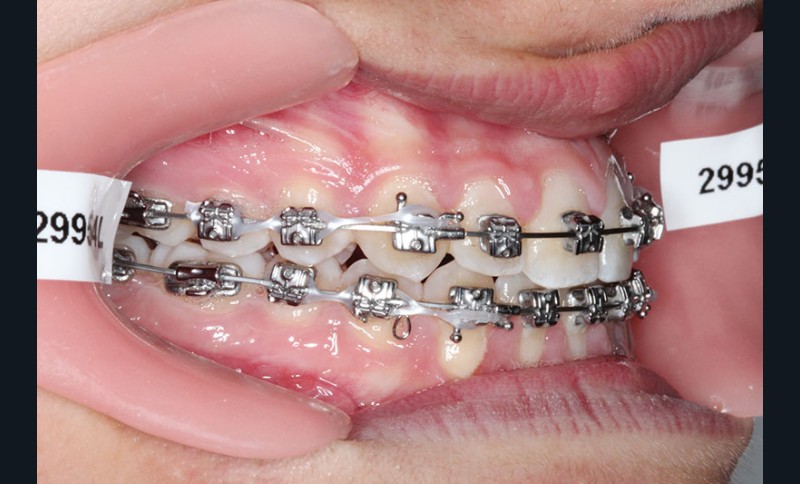

1re phase : recul des secteurs latéraux mandibulaires avec le Motion Classe III Carriere (fig. 4 à 6)

Nous mettons en place des bras latéraux Motion associés à des élastiques intermaxillaires ancrés sur des brackets sur 17 et 27 et une gouttière thermoformée maxillaire portée jour et nuit :

L’objectif de cette étape est d’obtenir un recul des secteurs latéraux mandibulaires afin de positionner les molaires et canines en classe I et de réorienter le plan d’occlusion en haut en avant.